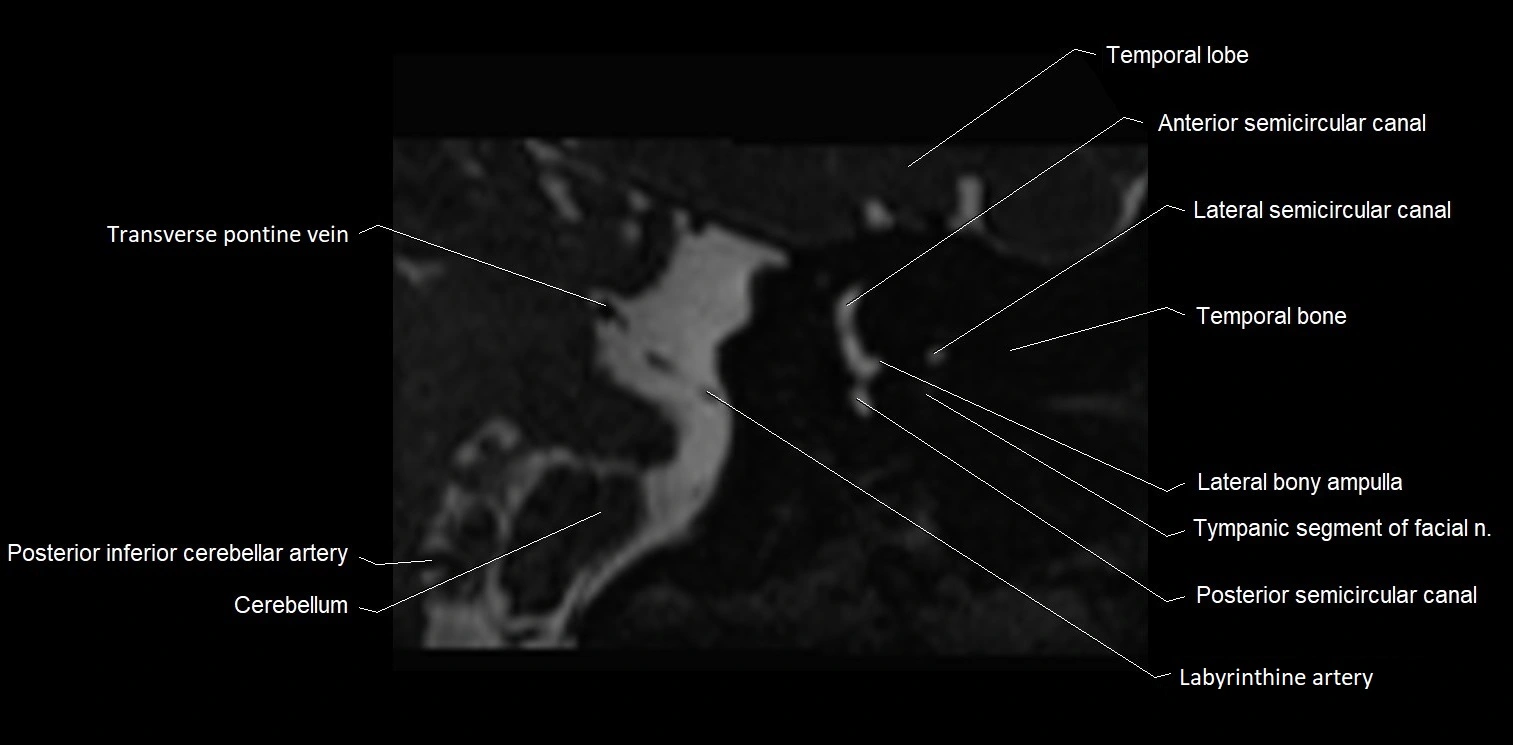

MRI Appearance

• The abducens nerve is a small, thin, linear structure

• Best visualized on high-resolution T2-weighted 3D MRI sequences (e.g., FIESTA or CISS)

• Seen as a hypointense (dark) line running from the brainstem at the pontomedullary junction, traversing the prepontine cistern, and entering Dorello’s canal under the petrosphenoidal ligament, then into the cavernous sinus, and finally the orbit

• May be challenging to visualize in standard MRI due to its small size

• Pathology may be inferred by absence, displacement, or enhancement of the nerve